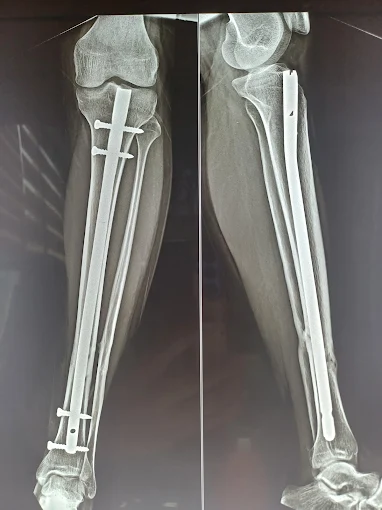

Trauma Surgery

Expert fracture and bone injury management with advanced surgical care

Bone Fracture Treatment

Specialized treatment and bone healing for all types of fractures

Fracture & Trauma Surgery

Expert management for complex fractures and trauma recovery

orthopaedic trauma

Comprehensive care for severe musculoskeletal injuries to restore stability and function